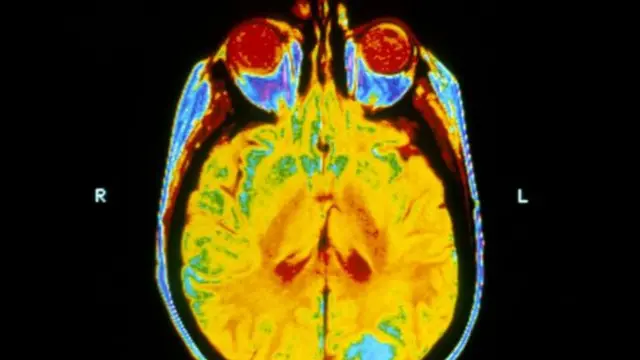

صدر الصورة، Science Photo Library